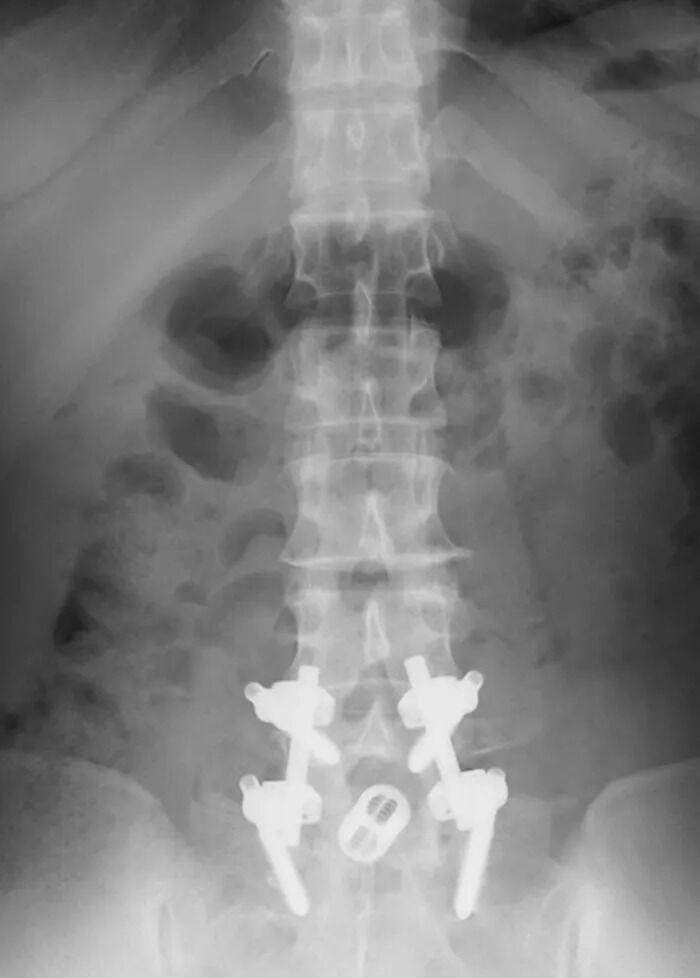

【超恐怖】長崎大、解剖遺体から『とんでもない物』を発見してしまう!!!!!